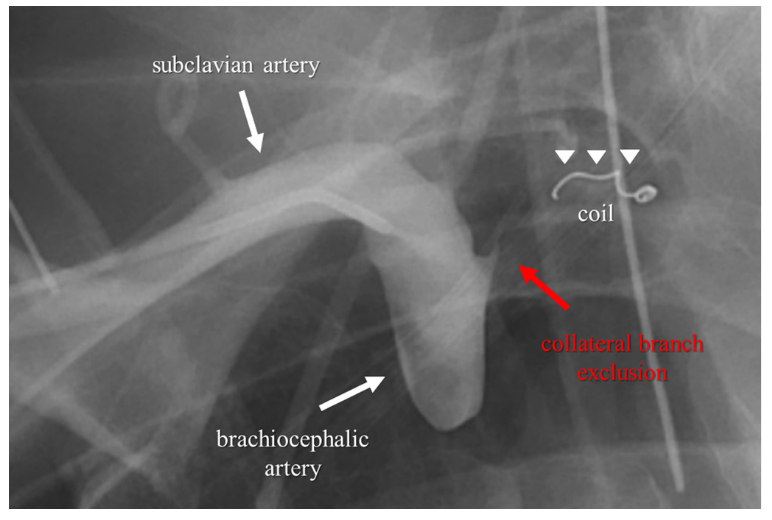

A 65-year-old man who presented with lateral ST-segment-elevation myocardial infarction was referred for primary percutaneous coronary intervention. J-wire and 5.2-Fr JR4 diagnostic catheter progression through right radial artery access was hampered by radial artery spasm and subclavian artery tortuosity. Then, a hydrophilic-coated guidewire was used to assist catheter advancement into the aortic root. Coronary angiography revealed an acute occlusion of the first obtuse marginal artery, which was successfully revascularized with 2 consecutive drug-eluting stents (Video Series). Three hours later, the patient developed symptoms of pleuritic chest pain, dyspnea, stridor, and evolved with shock. Thoracic computed tomography (CT) angiography revealed a large mediastinal hematoma compressing the airway (Figures 1C, 1E and Figure 2). Due to high index of suspicion and after multidisciplinary heart team discussion, an upper limb angiography was performed, which detected perforation of a small collateral branch of the brachiocephalic artery (Figure 1A). The perforation was treated with a single coil embolization, resolving the active bleeding (Figure 1B and Figure 3). Control CT imaging at 2-month follow-up revealed complete resolution of the mediastinal hematoma and airway compression (Figures 1D, 1F).

This clinical case illustrates an extremely rare and lethal complication of radial access PCI. We suspect the perforation was probably caused by the hydrophilic-coated guidewire. Mediastinal hematoma has scarcely been reported in the literature and, when present, the exact location of the bleeding was rarely identified. Rapid identification through chest imaging is crucial. In critically ill patients, endovascular management with coil embolization offers a less invasive and faster alternative to covered-stent implantation or surgery.